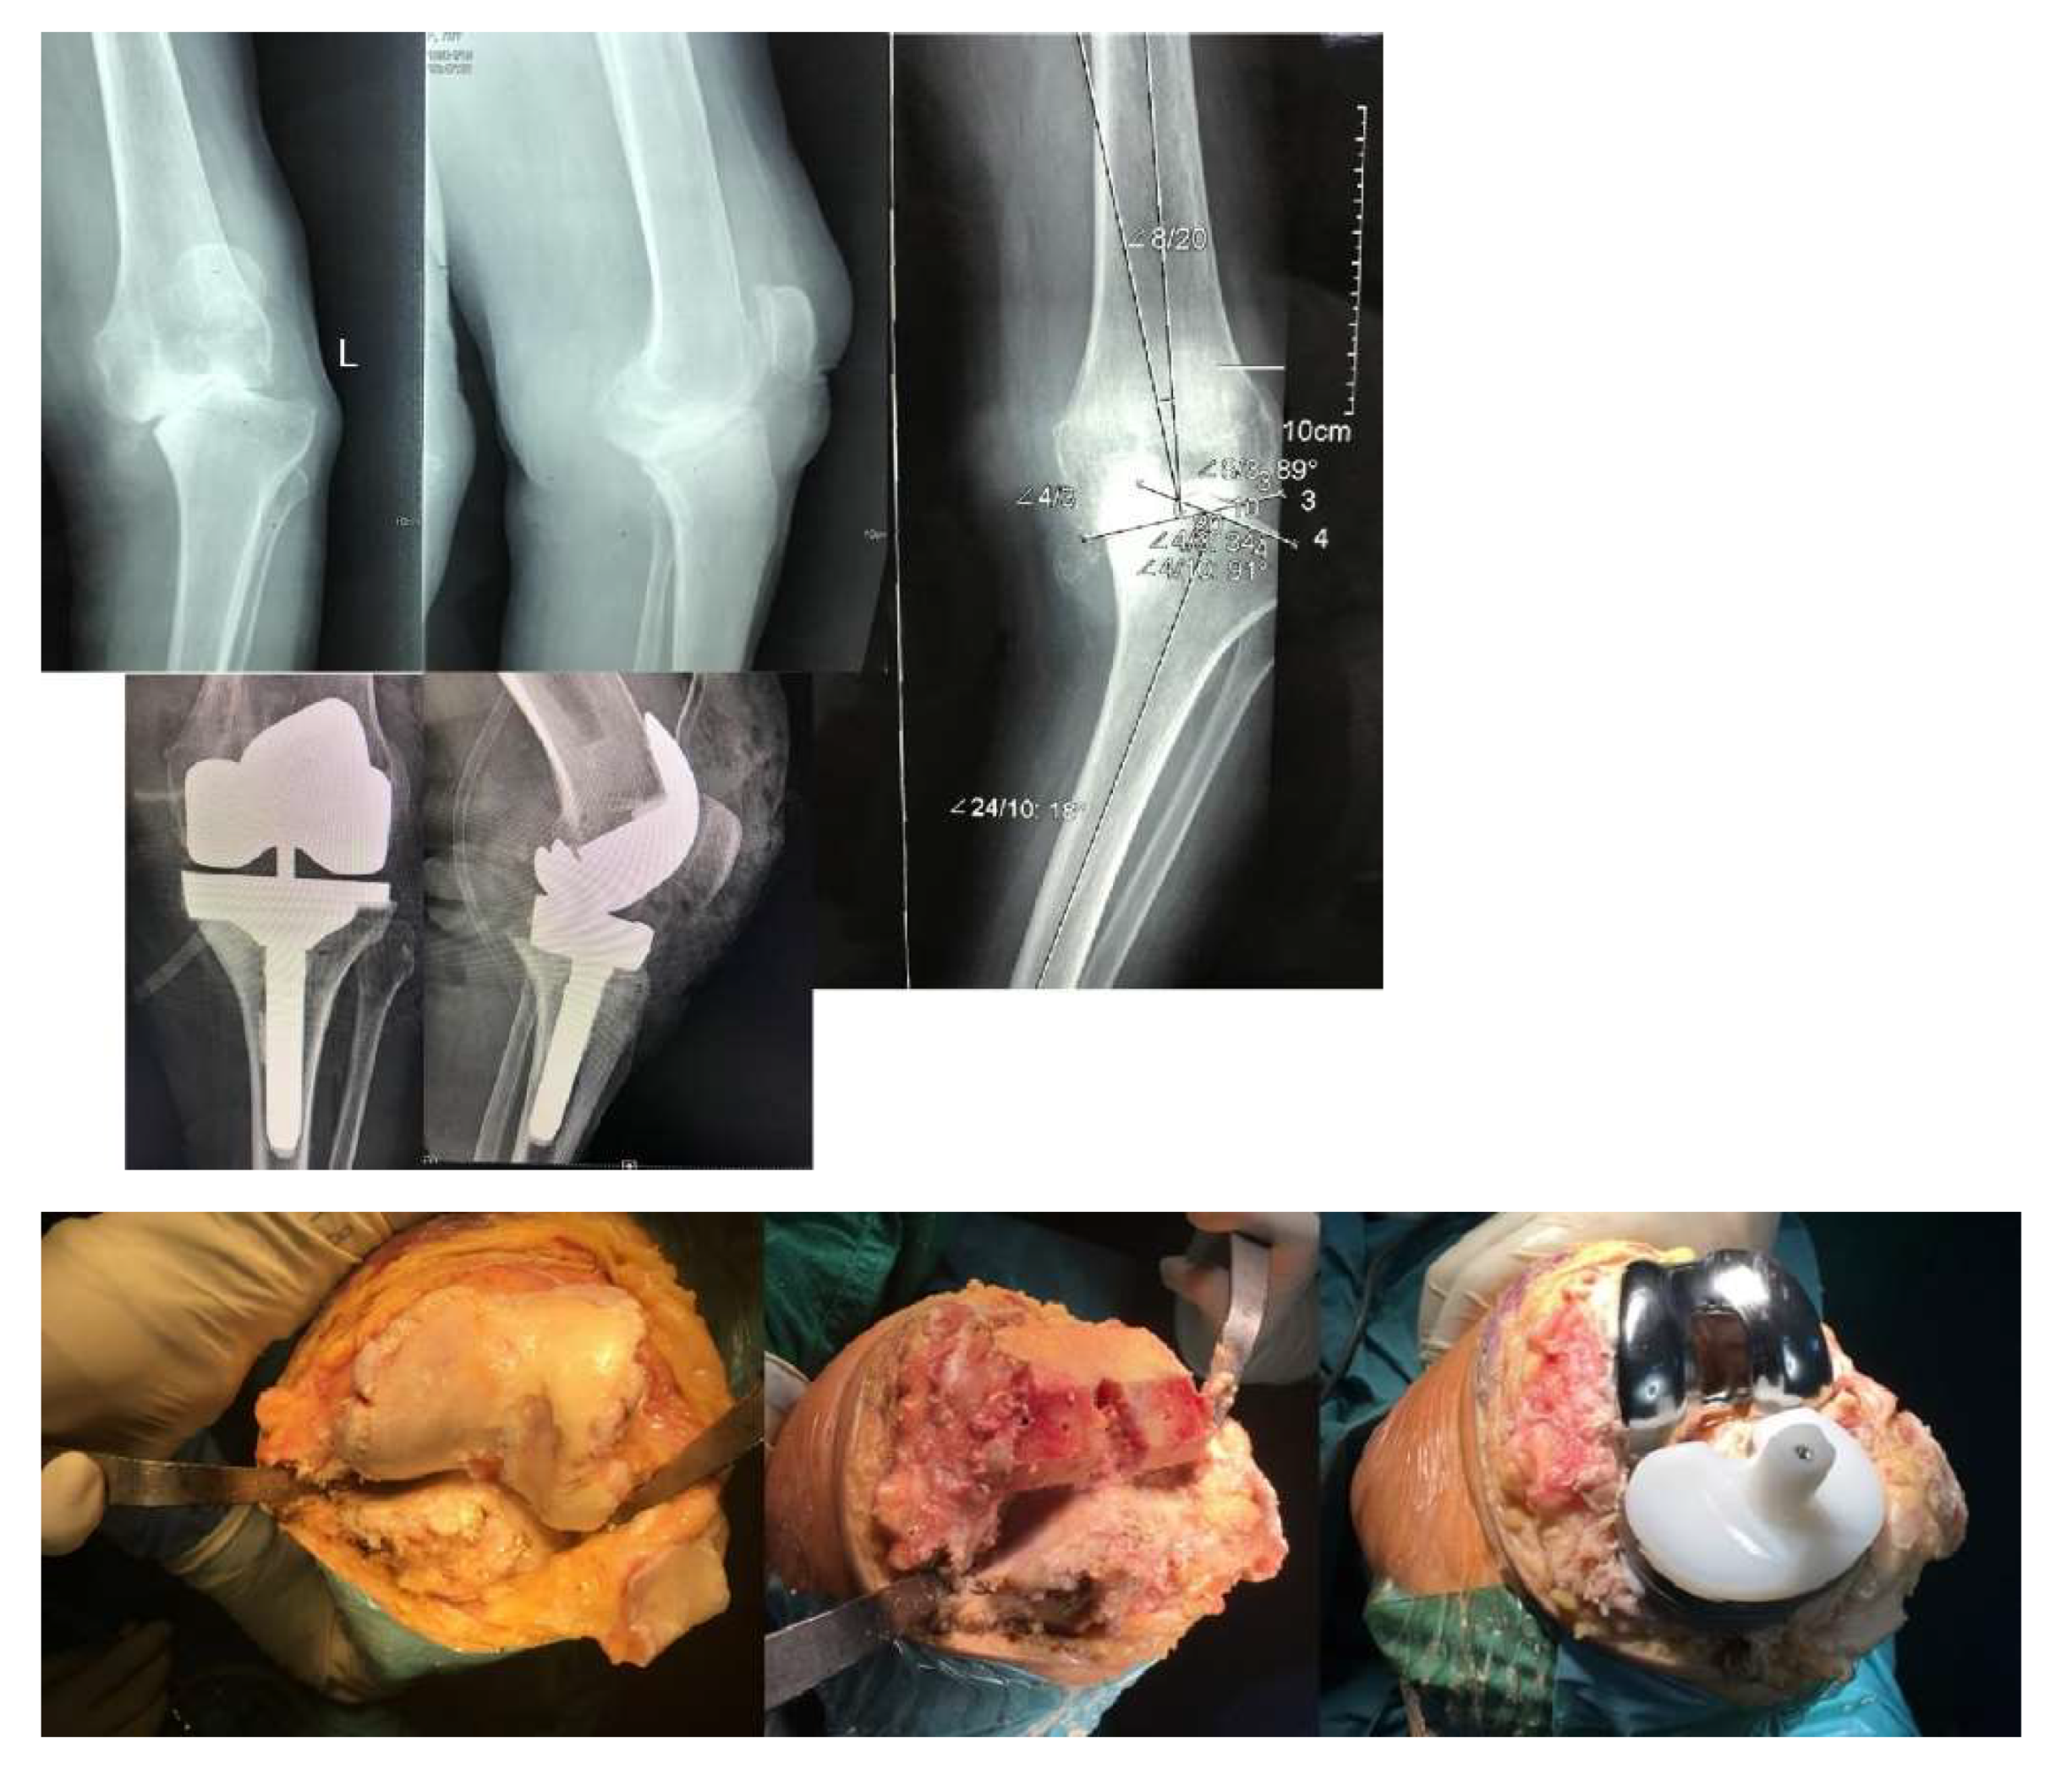

We illustrate here a primary case of TKA with valgus deformity on right knee, varus deformity on left knee - who necessitates the use of revision components with tibial stem extension with offset. (Fig. 5).

Another case with a 34° varum deformity that was treated by primary TKA with tibial stem extension is shown here. Intraoperative and postoperative X-rays are included (Fig.6).

Figure 6. X-rays taken during and after surgery show a significant deformity of 34° of varus that was corrected by a primary TKA with revision components.

Figure 5. Primary TKA with revision components tibial stem extension and offset, X-ray and clinical result.